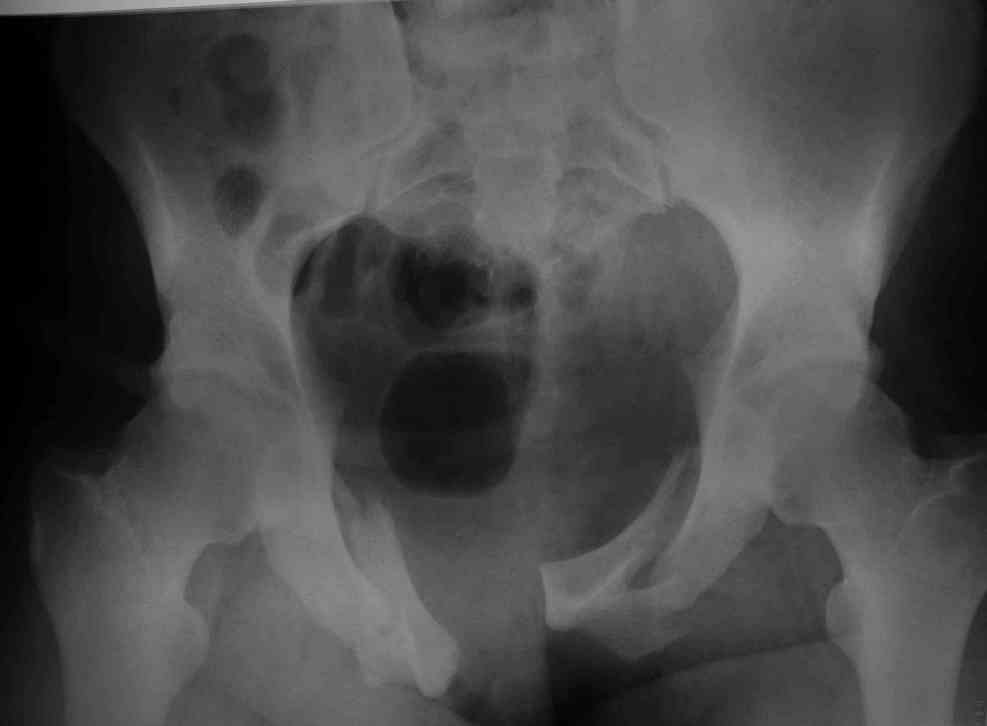

Уважаемые коллеги! опять вопрос по повреждению таза. Больной получил производственную травму 10 дней назад - удар балкой около 3 тонн в область верхней трети правого бедра и лона.

Был диагностирован перелом "типа бабочки" и повреждение уретры. Сделана цистостома. У насв отделении 3 дня. Имеется огромная флюктуирующая гематома с "галифе"-образной деформацией обеих бедер. Пнкционно эвакуировали в несколько приемов из подфасциальных полостей на бедрах около 3 литров геморрагического отделяемого с последующей эластической компрессией. При пункциях выявлено сообщение полостей на бедрах - видимо через поравннуюдиафрагму дна и полость таза - при удалении крови справа уменьшался объем левого бедра. Какой то активности проявялять покабоимся - аппаратная фиксация через отслоенные ткани представляется чреватой нагноением, открытая фиксация в условиях такой гематомы тоже не радует. Хотелось бы услышать ваше мнение

можно полечить в 2 этапа:как правило в области гребней гематомы все же не бывает, если гребни "свободны", то можно ограничиться на первом этапе передней рамой, вводя стержни через них (повреждение ротационно-нестабильное), затем после лечения отслаивающего повреждения Morel-Lavallee, выполнить открытую репозицию, внутреннюю фиксацию, возможно вместе с урологами. Тактику возможного лечения этой

Типичная картина Morel-Lavallee повреждения.

Безуспешны многочисленные шприцевые эвакуации, мы лечим в операционной, доступом на латеральной поверхности, открытием образования с удалением и очисткой полости щеткой. Закрываем с дренажной трубкой (в архивах сайта) и накладывается мягкая повязка Спика из нескольких слоев эластичной повязки.

Следующим этапом через 5-6 дней приступаем к фиксацию повреждения таза, иначе прооперериванные на фоне Morel-Lavallee повреждения осложняются инфицированием послеоперационной раны.

18.12. - отдельное спасибо еще раз А.В.Рункову- больного оперировали (А.В.Рунков) - произведен остеосинтез аппаратом - фиксация за крылья, два стержня в лонные кости и репозиция (почти полная) снимки будут чуть позже.

Дренировали отслойки на бедрах с их санацией. В правой ягодичной области сформировалась зона некроза. Больной "подвешен" за аппарат.